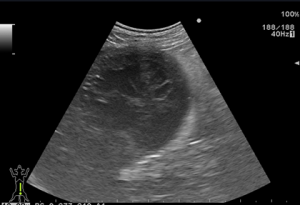

超音波検査:胆のう粘液嚢腫および周囲の腹膜炎が認められます。